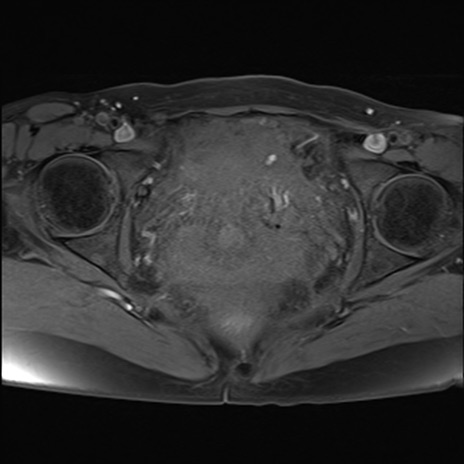

症例39 脂肪抑制T1WI(横断像)

MRI(4日後)

T1WI(横断像)